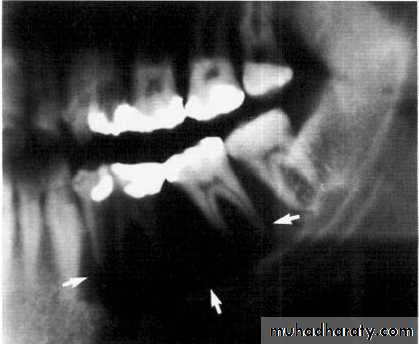

Traumatic cyst*Mandible > Maxilla. <20 years of age.

*Asymptomatic, expansile, associated with history of trauma. *Extend between the roots of teeth with scalloped border .

*Aspiration is not productive, empty cavity.